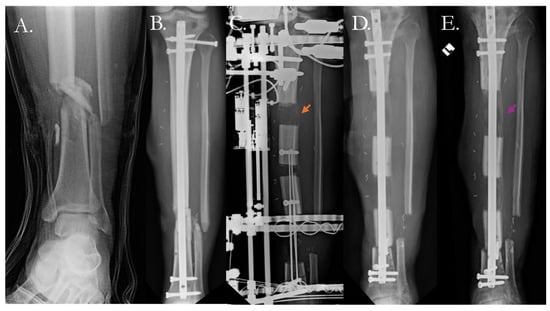

4.2.1. Traditional Surgical Approaches

4.2.2. Surgical Solutions with Biologic Therapy